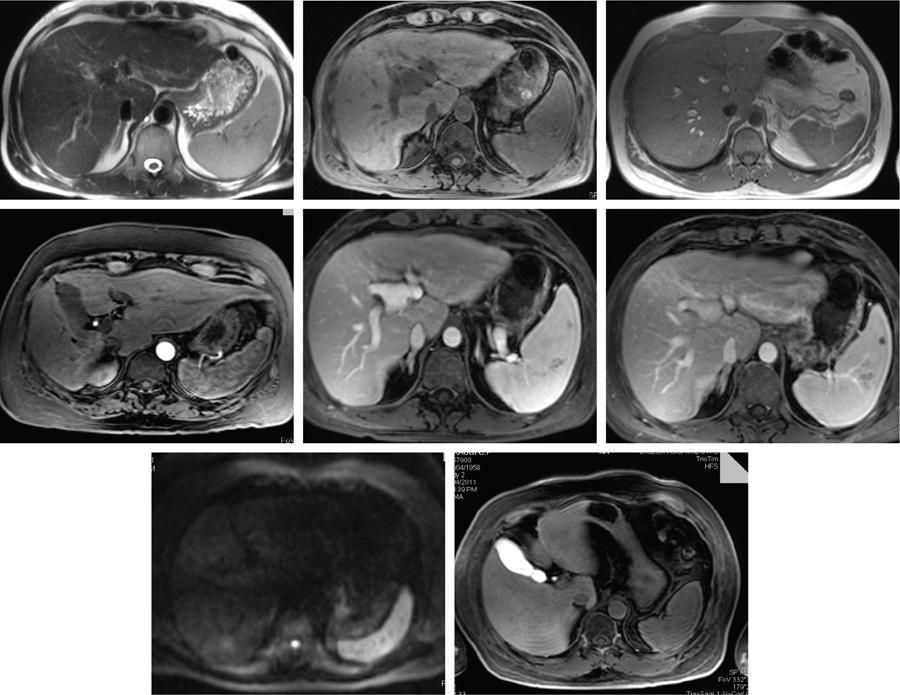

MRI

MR contrast agents